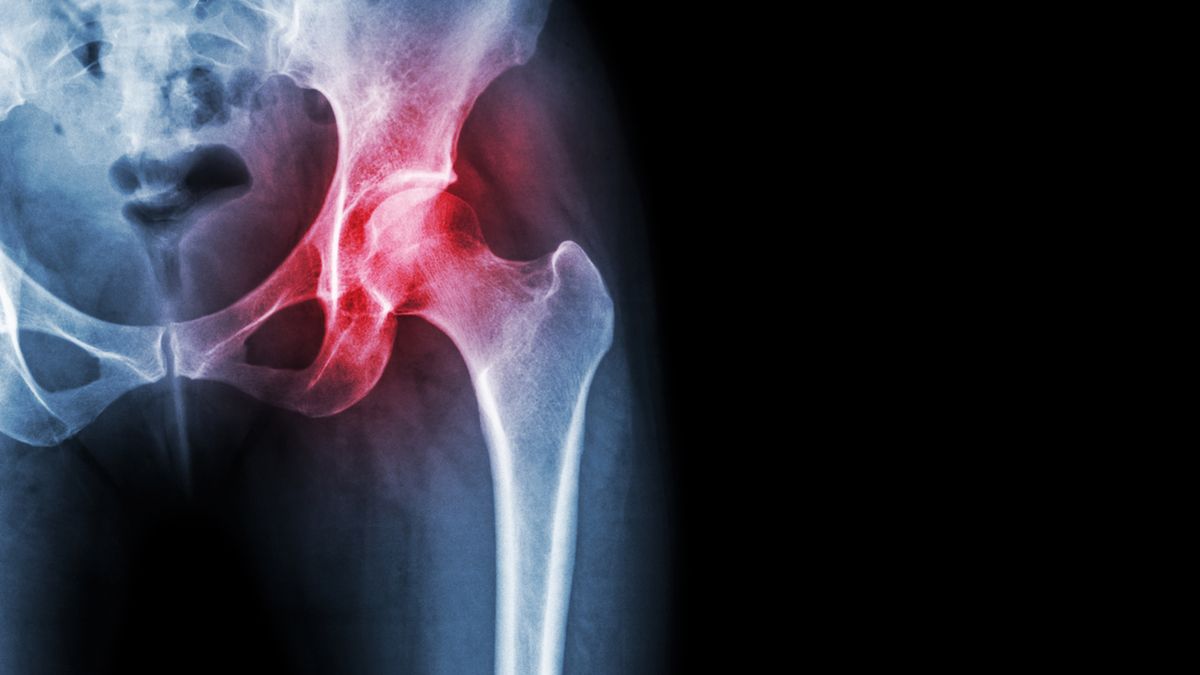

Zapalenie stawu biodrowego u dziecka rozpoznawane jest zwykle w wieku 2-8 lat.Zapalenie stawu biodrowego u dziecka rozpoznawane jest zwykle w wieku 2-8 lat.

Źródło zdjęć: © adobestock